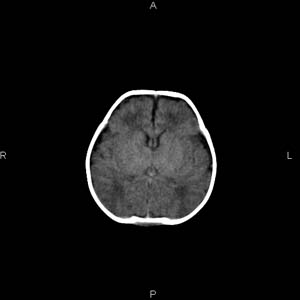

患者男,27天,出生后正常,今天中午在母亲怀里抱着吃奶在放下睡觉时发现后枕部慢慢出现一包块,来查头颅ct。无外伤史。包块内ct值47-51hu。请大家讨论。

1脑膜膨出可能性大 2产伤所致枕骨骨缝分离、头皮肿胀不除外,

建议:枕骨(下部)薄层扫描。

支持脑膜脑膨出,双侧侧脑室三角区周围脑白质对称性低密度影,考虑缺血缺氧性脑病或肾上腺性脑白质营养不良。